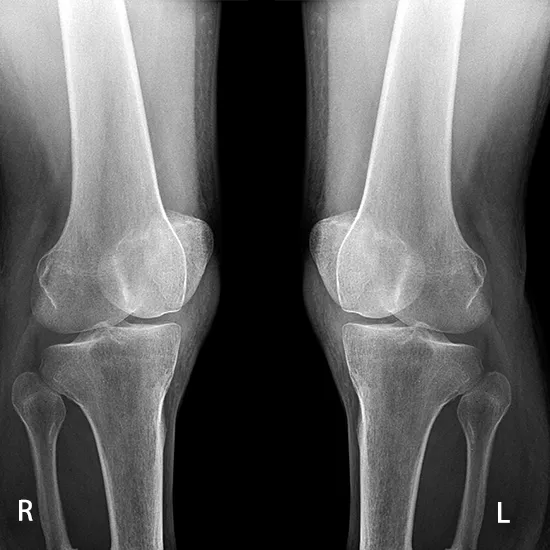

X-ray Both Knee Oblique - Test, Procedure & Cost

X-Ray Both Knee Oblique

The oblique knee view is an extra projection that is asked for when a complete look at the knee joint is needed. There is both an interior oblique and an exterior oblique. Inside and outside oblique views of the knee can show fractures and changes in the bone caused by wear and tear.